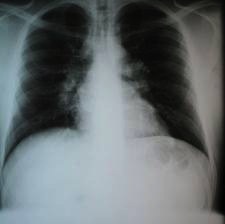

Parmi le bilan réalisé revient l’examen suivant.

Question 9 : Vous identifiez sur cette radio :

Il faut différencier la vascularisation physiologique visible en radiographie de micronodule et condensation

Le calibre des bronches souches est normal. L’adénopathie n’est pas compressive.

Question 10 : Devant les éléments ci-dessus, quel(s) diagnostic(s) est (sont) plausibles ?

Vrai, dans une forme ganglionnaire ; même si beaucoup moins probable à ce stade que la sarcoïdose.

Vous suspectez fortement une sarcoïdose mais vous ne pouvez pas éliminer une tuberculose.